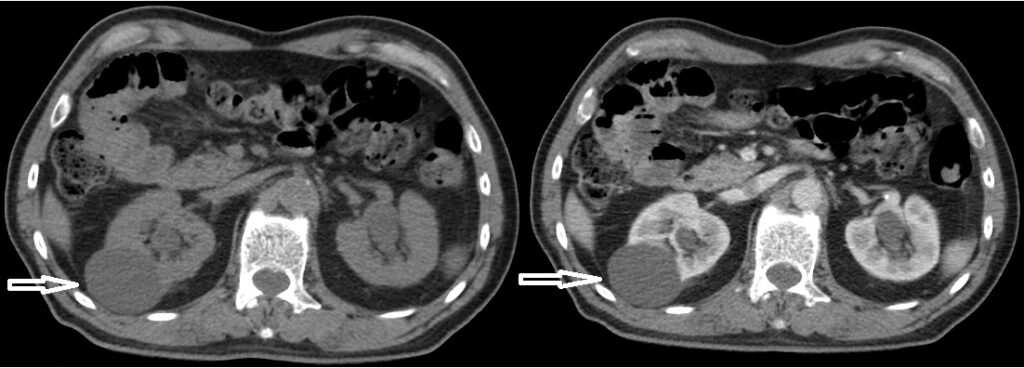

5. Estadificación

La importancia de la identificación y el uso de la TCMC como método de estudio para el CCR radican en poder planificar un mejor tratamiento del paciente. Para esto se utiliza a estadificación propuesta en 2009 por la Asociación Europea de Urología1 conocida como “estadificación TNM” donde T equivale al tamaño y ubicación del tumor, N a la afectación o diseminación linfática y M a las metástasis del mismo. En base a la TNM se establecen 4 estadios con su respectiva supervivencia a 5 años 1-11 (Tabla 1).

Para tratar de detectar las metástasis por el CCR es importante tener en cuenta los sitios y la frecuencia en que se manifiestan:

- Pulmón (50% -60%)

- Huesos (30% -40%)

- Hígado (30% -40%)

- Glándula suprarrenal, riñón contralateral, retroperitoneo y cerebro (5% cada uno).